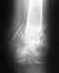

7лет назад ломала на ноге мезинец в 2-х местах,говорят косточка срослась неправильно.теперь нарастает хрящевая ткань.

эта шишка мешает ходить,натирает между пальцев.Можно ли её удалить у вас в клинике.сообщите на e-mail .и как к вам можно записаться на приём.цены.спасибо.жду.